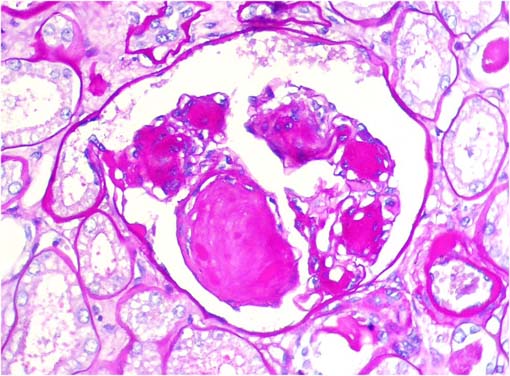

Figura 3.

Tricrómico de Masson, X400.